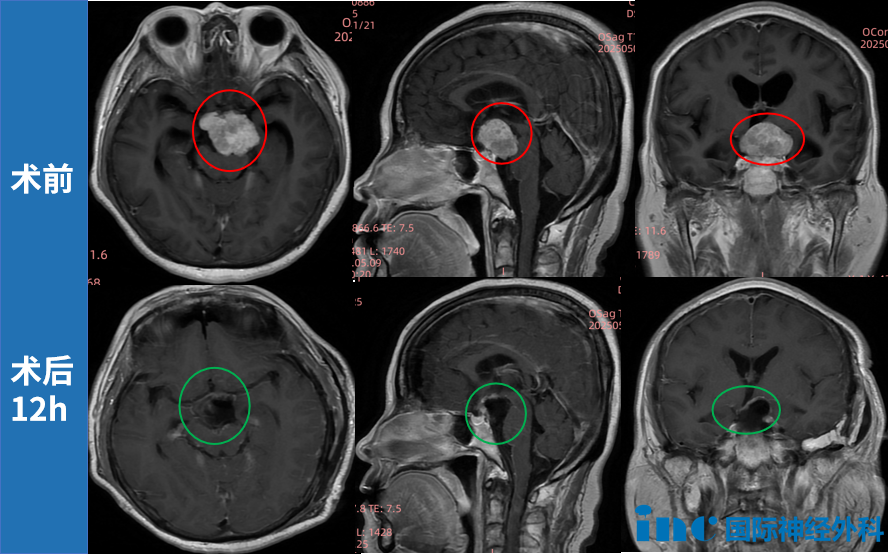

一枚32×30×29毫米的鞍区肿瘤,向前上方挤压视交叉、向前下方压迫垂体柄、向后方推挤脑干;与动眼神经、滑车神经、三叉神经紧密缠绕,紧邻颈内动脉和基底动脉系统——解剖关系之复杂,堪称教科书级别。

以上仅是术前筹备阶段的工作。进入手术室后,术者以功能保护为第一原则进行精细化操作,最终这枚肿瘤被顺利满意地全切切除,患者术后恢复状况良好。